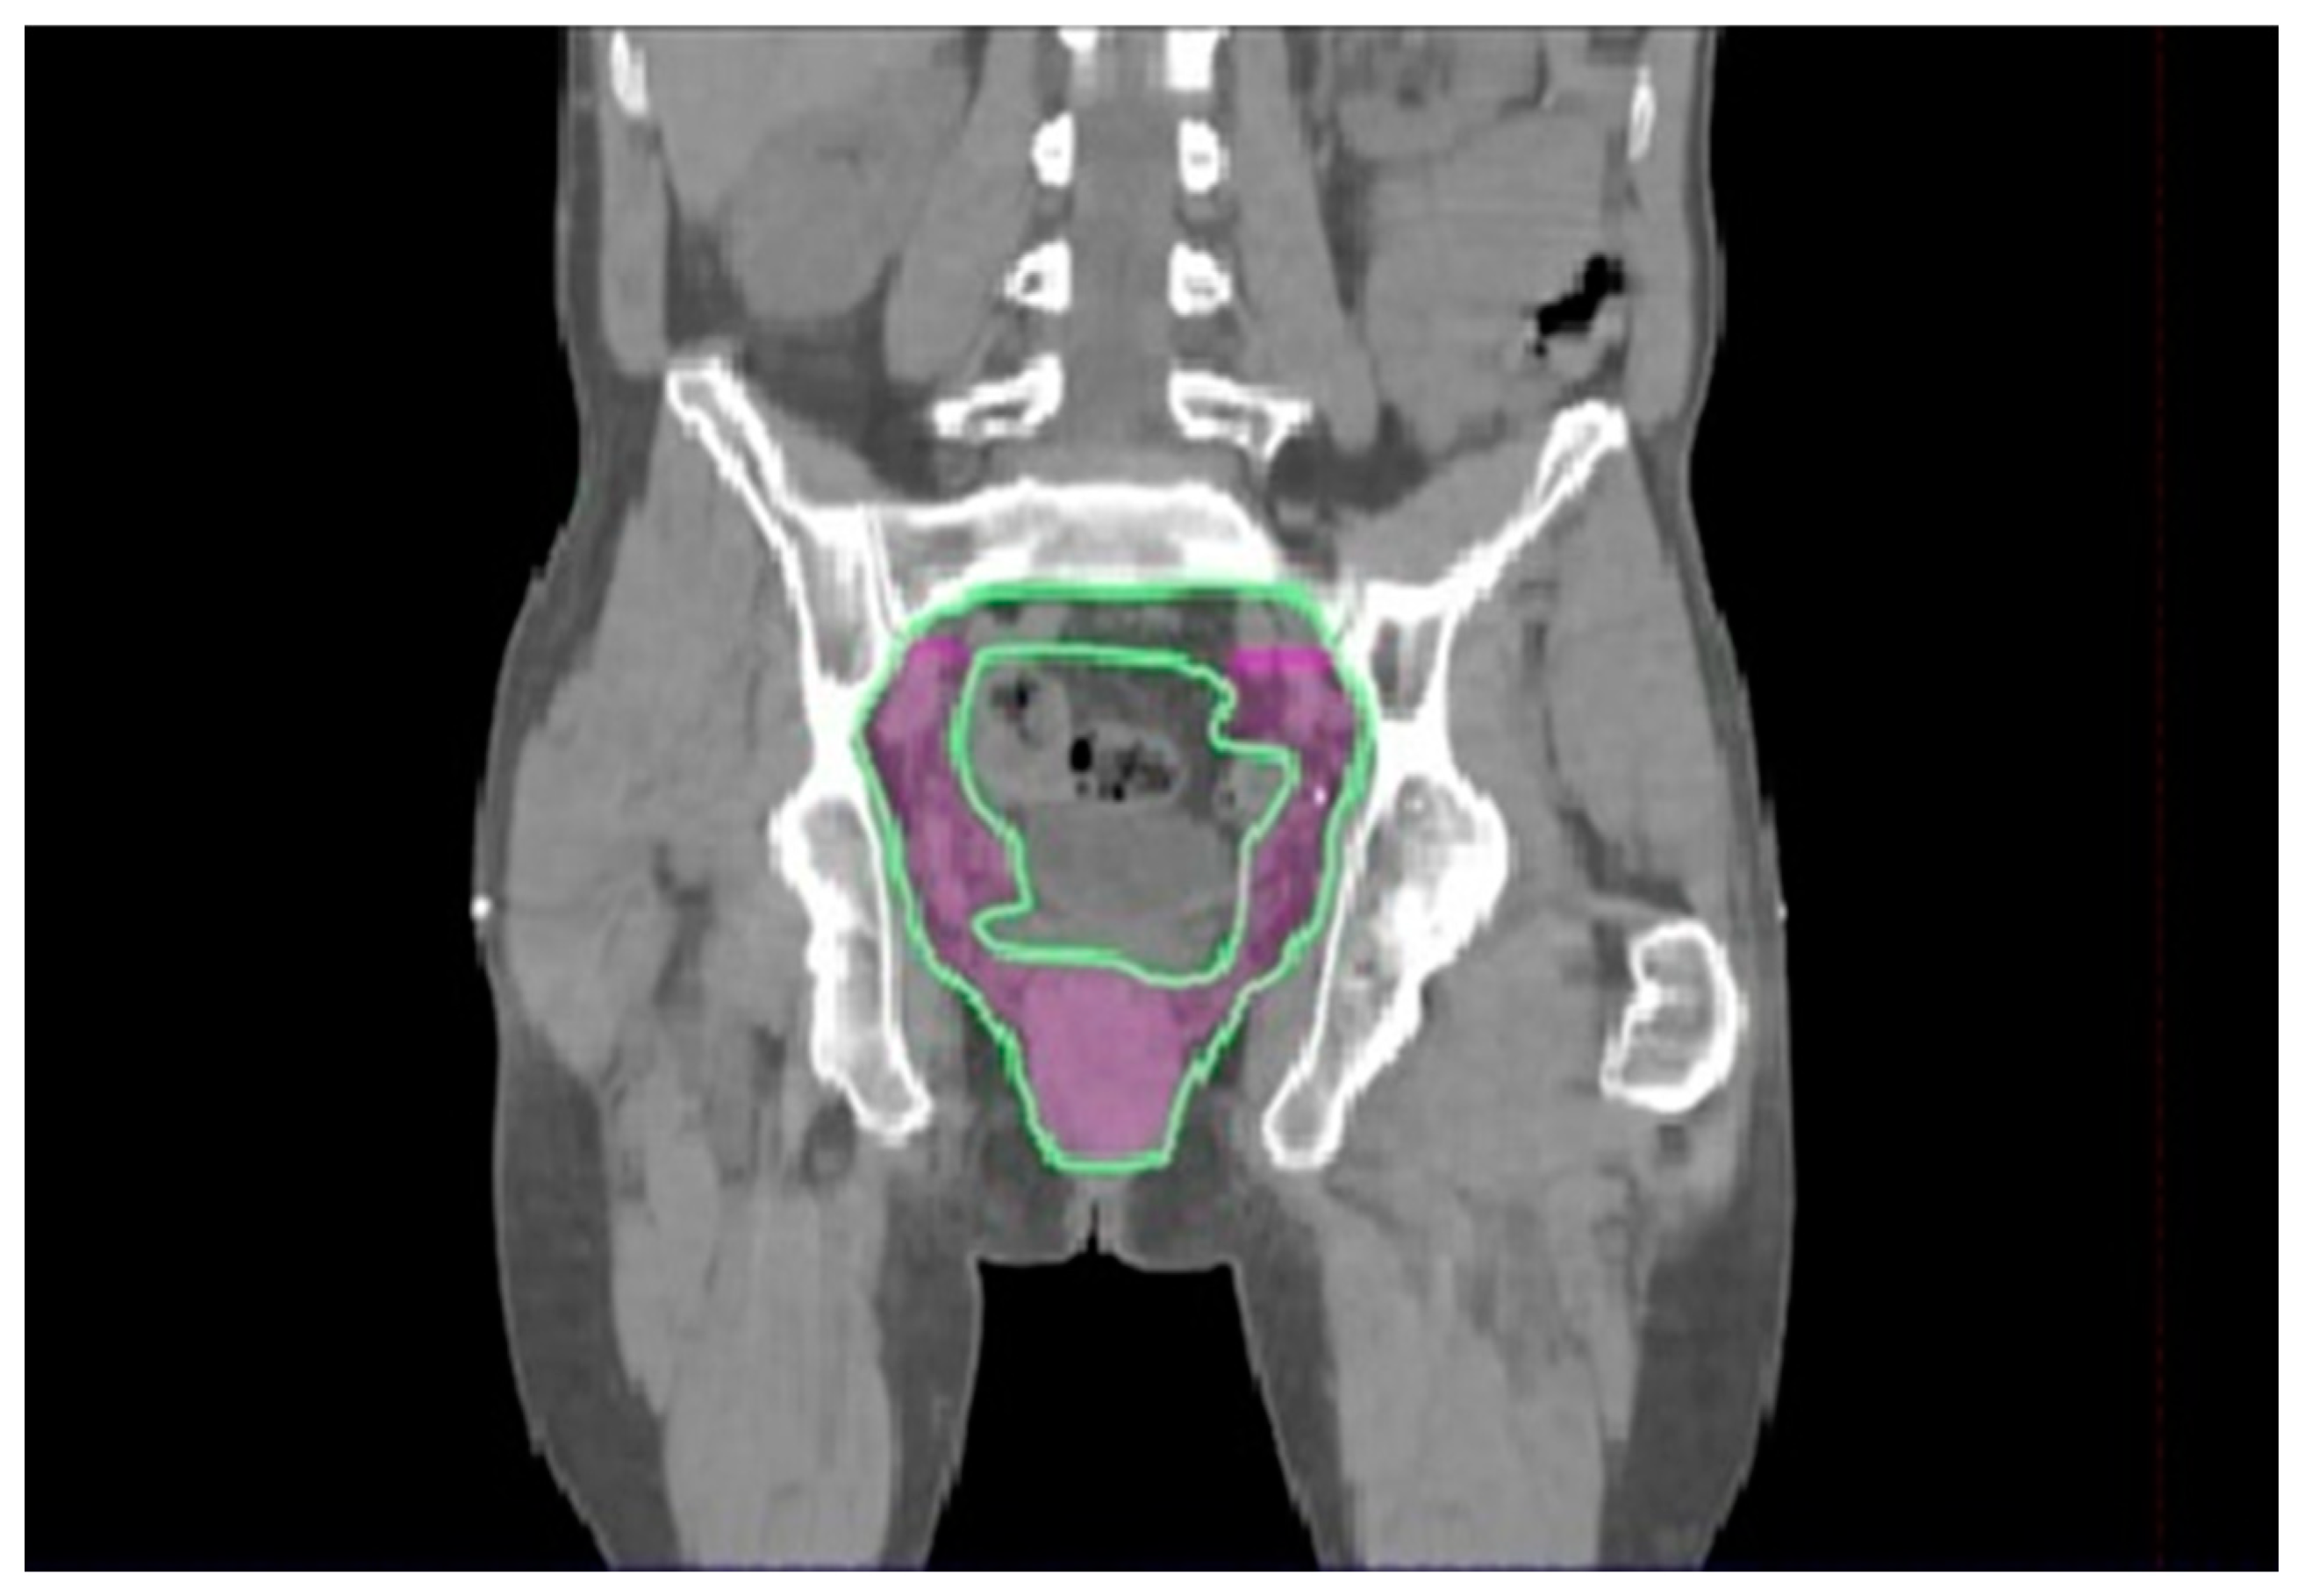

3.2. Radiotherapy Volumes

3.2.4. External Iliac Level

3.2.5. Pararectal, Presacral, and Internal Iliac Nodes

- The external iliac node station should remain as a part of the adjuvant treatment, at least for patients with larger tumors (T2 or bigger).